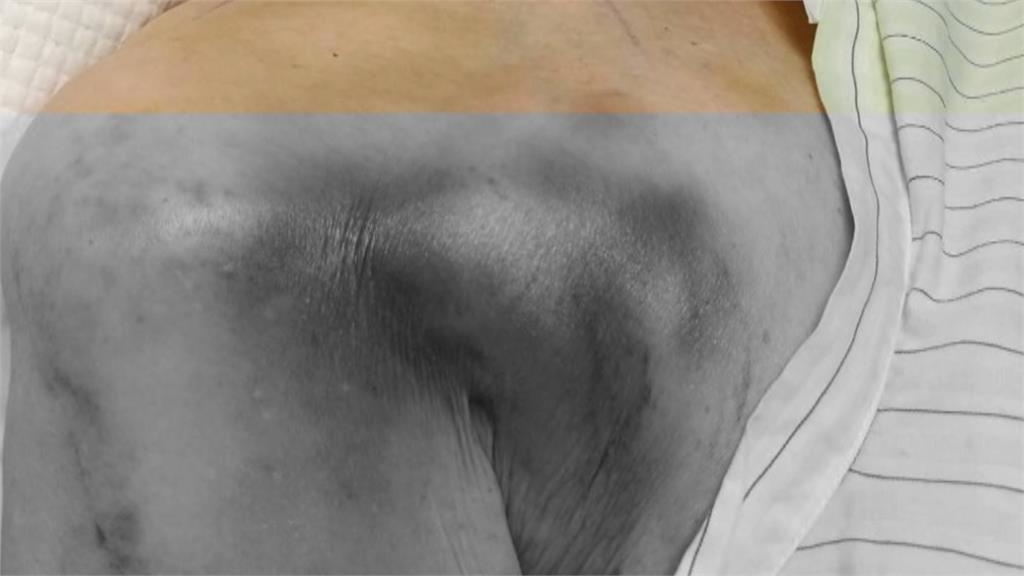

94歲的老母親,坐在輪椅上,表情有些痛苦,仔細一看,竟發現身體莫名出現大面積瘀青,家屬無法理解,母親的傷,到底哪裡來的?女兒驚見媽媽手臂,腹部,大腿等部位都出現瘀青,心中既傷心又難過,詢問護理之家,卻得到這樣的答案。